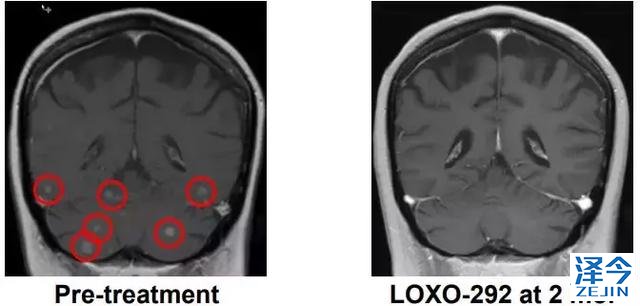

M女士走图无路的情况下接受了基因检测,发现了KIF5B-RET融合,开始接受600 mg BID靶向药 alectinib治疗(PR,7个月),由于脑转移进展增加至900mg BID,后脑转移症状严重,M女士接受了LOXO-292治疗,于是奇迹出现了,治疗两个月后,M女士肺部的病灶明显好转,脑部病灶几乎全部消失!